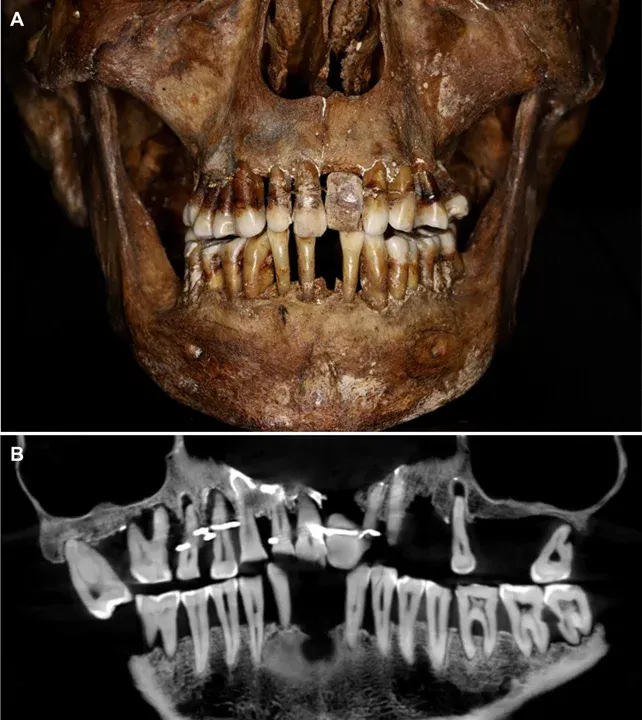

ร่างของ Anne d'Alegre ซึ่งเสียชีวิตในปี 1619 ถูกค้นพบระหว่างการขุดค้นทางโบราณคดีที่ปราสาทลาวาล ทางตะวันตกเฉียงเหนือของฝรั่งเศส ในปี 1988 พระศพของเธอถูกบรรจุในโลงตะกั่ว โดยโครงกระดูกและฟันของเธอได้รับการเก็บรักษาไว้อย่างดีอย่างน่าทึ่ง ในเวลานั้น นักโบราณคดีสังเกตเห็นว่าเธอมีฟันปลอม แต่พวกเขาไม่มีเครื่องมือสแกนที่ทันสมัยเพื่อค้นหาข้อมูลเพิ่มเติม

35 ปีต่อมา ทีมนักโบราณคดีและทันตแพทย์ได้ระบุว่า d'Alegre ป่วยด้วยโรคปริทันต์ซึ่งทำให้ฟันของเธอโยก โดยศึกษาด้วยการสแกนแบบ "Cone Beam" ซึ่งใช้รังสีเอกซ์เรย์สร้างภาพสามมิติ แสดงให้เห็นว่าลวดทองคำถูกนำมาใช้ยึดฟันของเธอหลายซี่เข้าด้วยกัน เธอมีฟันปลอมที่ทำจากงาช้างด้วย ไม่ใช่จากฮิปโปโปเตมัส ซึ่งเป็นที่นิยมในสมัยนั้น แต่การพยายามทำให้ฟันนั้นอยู่ครบก็ไม่ใช่เรื่องดีนัก นักวิจัยกล่าวว่าลวดทองคำจะต้องขันให้แน่นซ้ำแล้วซ้ำเล่าเป็นเวลาหลายปี ส่งผลให้ฟันข้างเคียงไม่แข็งแรงมากนัก